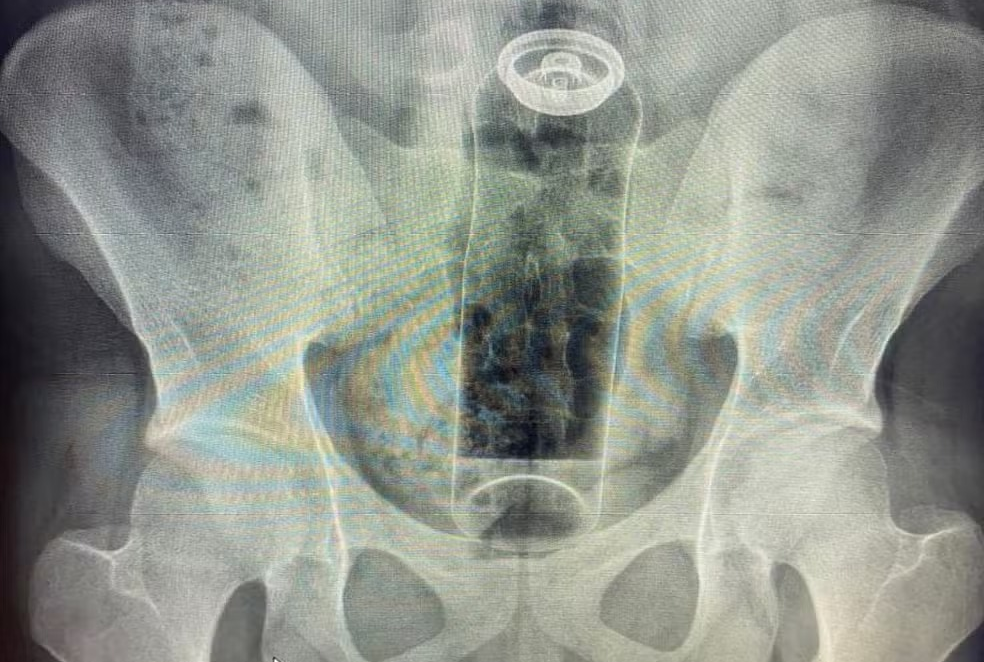

Jovem é internado após desodorante ficar preso no reto

Um jovem de 19 anos precisou ser internado após ficar com um desodorante preso no reto durante uma prática sexual. O caso foi relatado pelo cirurgião coloproctologista Daniel Brosco, que atendeu o paciente após a embalagem subir para o reto e não conseguir ser retirada em casa. O médico compartilhou o atendimento nas redes sociais como forma de alerta.

Segundo o especialista, objetos que não são próprios para uso anal podem ser “sugados” pelos movimentos peristálticos do intestino ou pelo vácuo formado na região, o que dificulta a retirada e pode exigir procedimentos hospitalares. Ele informou que já atendeu casos envolvendo outros objetos, como garrafas, partes de móveis, alimentos e plugs anais, alguns deles associados a infecções graves.